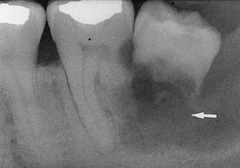

Root resorption (radiographic terms used to describe lesions in bone)

Front

Observed radiographically when the apex of the tooth appears shortened or blunted and irregularly shaped; occurs as a respons to simuli, which can include a cyst, tumor, or trauma.